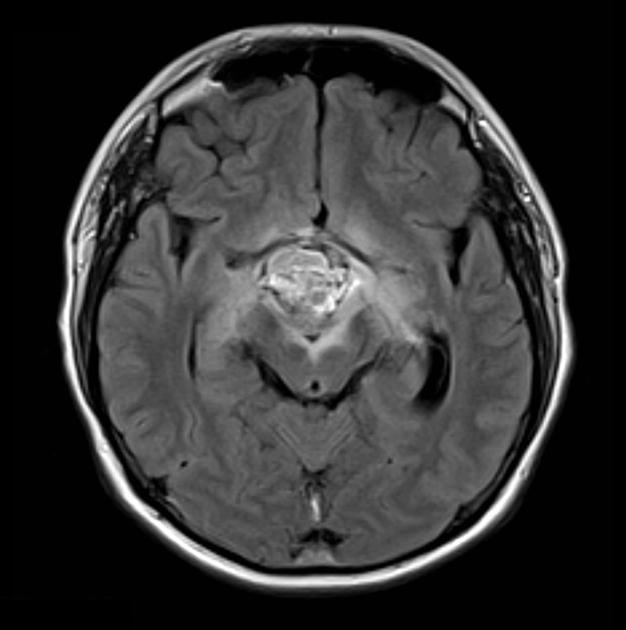

• U sọ hầu dạng Adamantinoma (Adamantinomatous Craniopharyngioma)